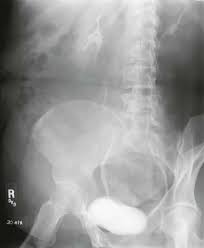

Oblique Kidney X Ray. The presence of calcifications kidney stones in the kidneys or ureters may be noted. Abdominal x ray will demonstrate most cases of bowel obstruction by showing dilated bowel loops.

Ectopic Kidney Radiology Reference Article Radiopaedia Org

Basic information regarding the size shape and position of the kidneys ureters and bladder may be obtained with a kub x ray. A kidney ureter and bladder kub study is an x ray study that allows your doctor to assess the organs of your urinary and gastrointestinal systems. The kidneys are located on the posterior abdominal wall with one on either side of the vertebral column in the perirenal space. The long axis of the kidney is parallel to the lateral border of the psoas muscle and lies on the quadratus lumborum muscle.